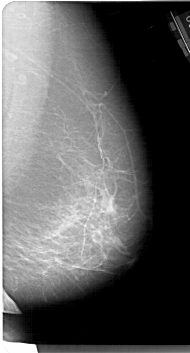

A_1190_1.LEFT_MLO

LEFT_MLO LINES 6826 PIXELS_PER_LINE 3886 BITS_PER_PIXEL 12 RESOLUTION 43.5 OVERLAY